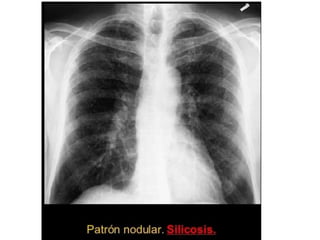

4. Nodular (< 6 cms): metástasis

Neumocomiosis